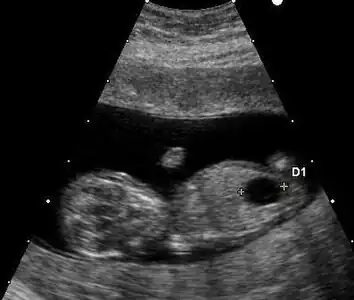

Prenatal ultrasound can be used to screen for Down syndrome. Findings that indicate increased chances when seen at 14 to 24 weeks of gestation include a small or no nasal bone, large ventricles, nuchal fold thickness, and an abnormal right subclavian artery, among others.[113] The presence or absence of many markers is more accurate.[113] Increased fetal nuchal translucency (NT) indicates an increased possibility of Down syndrome picking up 75–80% of cases and being falsely positive in 6%.[114]

Ultrasound of fetus with Down syndrome showing a large bladder

Enlarged NT and absent nasal bone in a fetus at 11 weeks with Down syndrome